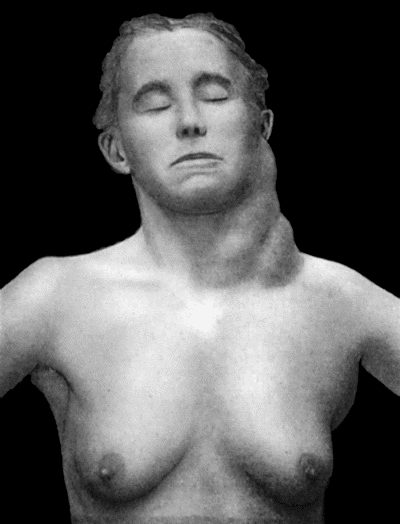

| 80. | Chronic Hodgkin's Disease in boy æt. 11 | 337 |

| 81. | Lymphadenoma in a woman æt. 44 | 338 |